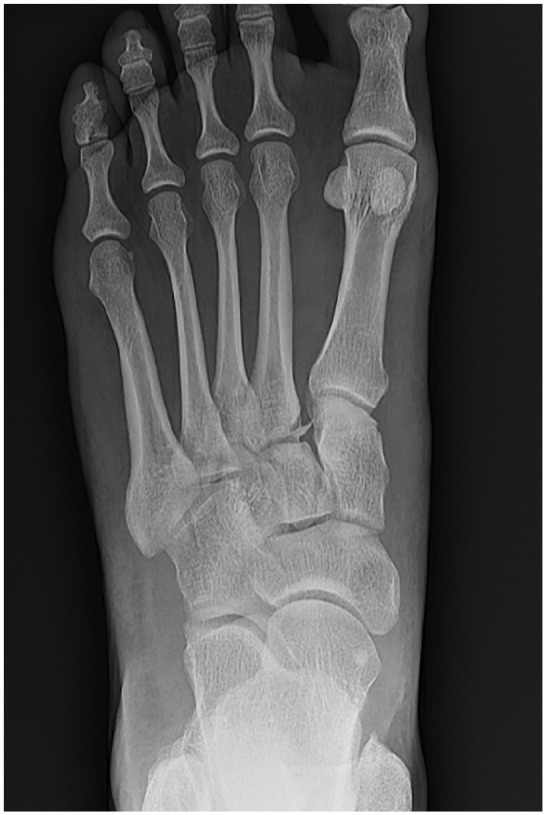

Methods: This study included patients who had a nondislocation Lisfranc injury with a proximal first webspace (between the medial cuneiform and second metatarsal base) diastasis of 2-5 mm, and underwent either a primary ORIF or primary arthrodesis. Preoperative weightbearing radiographs were reviewed to confirm subtle Lisfranc injuries. Of the 73 patients who met the inclusion criteria, 41 received a PA and 32 received an ORIF. Treatment selection was based on surgeon preference. Patient-reported outcomes via PROMIS scores were collected preoperatively and at least 2 years postoperatively. Subsequent procedures were also recorded.